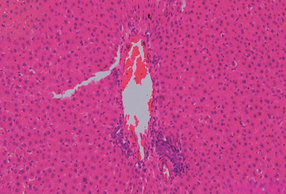

Ripara & Proteggi, con tecnologia NovaMin, è in grado di creare uno strato minerale protettivo, sulla parte esposta della dentina, ovvero una barriera riparativa e difensiva caratterizzata da una struttura cristallina, principale costituente minerale del tessuto del dente.

Questa particolare tecnologia BIOATTIVA si attiva al contatto con la saliva e aiuta a riparare le aree sensibili in cui la dentina (la parte che si trova sotto lo smalto e che contiene i tubuli dentinali) è esposta, utilizzando calcio e fosfato, gli stessi minerali di cui sono fatti i denti.

Sensodyne Ripara & Proteggi, con NovaMin, crea uno strato minerale protettivo sulla dentina che si rafforza con l’uso regolare del prodotto e aiuta a prevenire il dolore provocato dalla sensibilità dentinale.